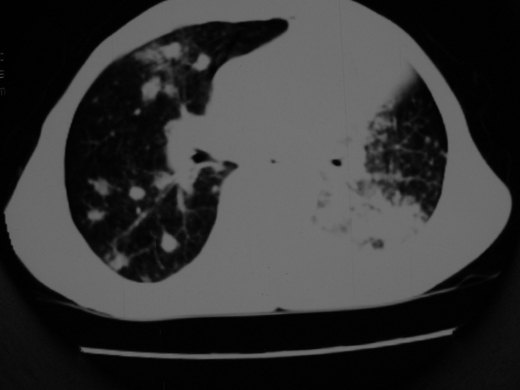

男69岁,年前胸片示肺感染治疗近一月今复查无明显好转,血象正常

双肺内不规则斑点状 片状及结节密实影,部分灶周见索条样影及\"树芽征\",左肺上叶实变,内见充气支气管影及斑状钙化,左侧少量胸腔积液,考虑1)双肺结核2)左侧胸腔积液

右肺多发片絮状结节状及时条索状影,左上肺实变,内可见虫蚀样空洞及支气管气象,左下肺片状及球形病灶,及胸腔积液征象,双肺病灶内多发钙化影,结合病史,考虑双肺继发型肺结核,左胸腔积液

右肺多发片絮状结节状及时条索状影,左上肺实变,内可见虫蚀样空洞及支气管气象,左下肺片状及球形病灶,及胸腔积液征象,双肺病灶内多发钙化影,上纵隔向左侧移位,结合病史,考虑双肺继发型肺结核,左胸腔积液。

右肺多发片絮状、结节状及条索状影,左上肺实变,内可见虫蚀样空洞及支气管气象,左下肺片状及球形病灶,有胸腔积液征象,双肺病灶内多发钙化影,上纵隔向左侧移位,结合病史,考虑双肺继发型肺结核,左胸腔积液。 建议结合ppd检查或纤支镜检查!

右肺可见大片状、云絮状改变。右肺可见散在类圆形影,以外带多见。左肺实变,其内可见明显支气管走行影。纵隔淋巴结有增大,左侧胸腔积液。考虑1、肺结核;2、肺癌肺转移不除外;3、左侧胸腔积液。